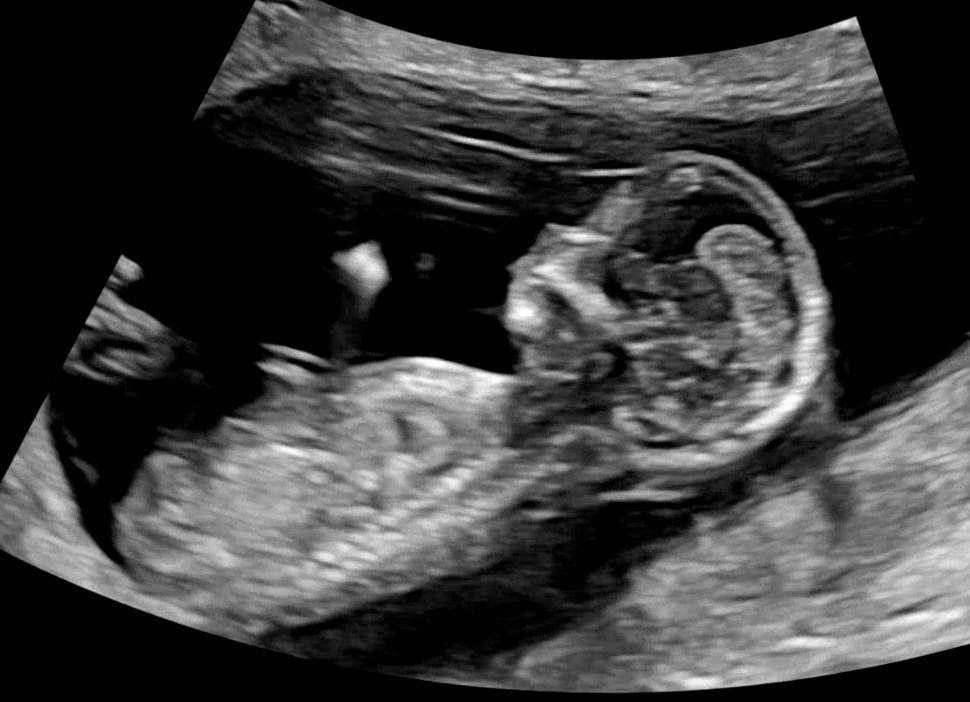

12주 4일차인데 각도법 한번 봐주세요!

저는 잘모르겠어서 부탁드려요!😍😍